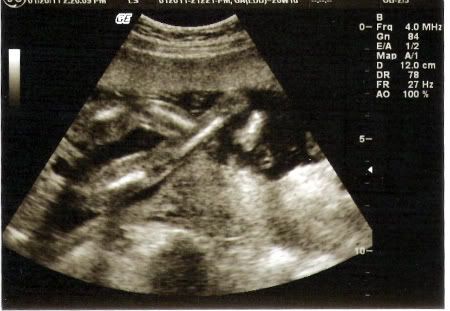

But baby girl T is measuring right on time (to the day!) and everything looked great so far. She weighs nearly a pound now, which is hard to believe! And she has definitely changed a LOT since we saw her a month ago! The u/s tech also pointed out her looooong legs, which was so cute to see. She definitely gets that from my side of the family! And here are two pictures I love. We couldn't get any great ones of her face because she was laying on my bladder and covering her face with her hands.

crossing her legs!